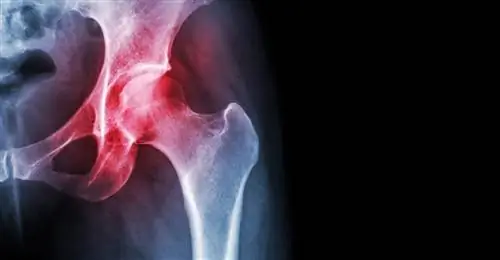

Искусственные тазобедренные суставы - очень хорошее решение, но, к сожалению, не навсегда. Хотя они изготовлены из таких прочных материалов, как керамика и титан, их недостаточно, чтобы прослужить всю жизнь, особенно если они имплантированы молодому человеку. Особенно хлопотно расшатывание частей, закрепленных в живой кости, которое может произойти через несколько лет. Причиной являются мягкие ткани, образующиеся вокруг металлических деталей. Стволовые клетки способствуют этому.

Ученые хотят покрыть важные поверхности протезов пластиковым нанорисунком, чтобы побуждать стволовые клетки формировать кость при контакте с новым суставом. Особый рисунок наноточек из полимера с сокращенным названием PEREK (полиарилэфиркетон) заставляет вокруг имплантата формироваться кость, а не мягкая ткань. Это снижает риск расшатывания.